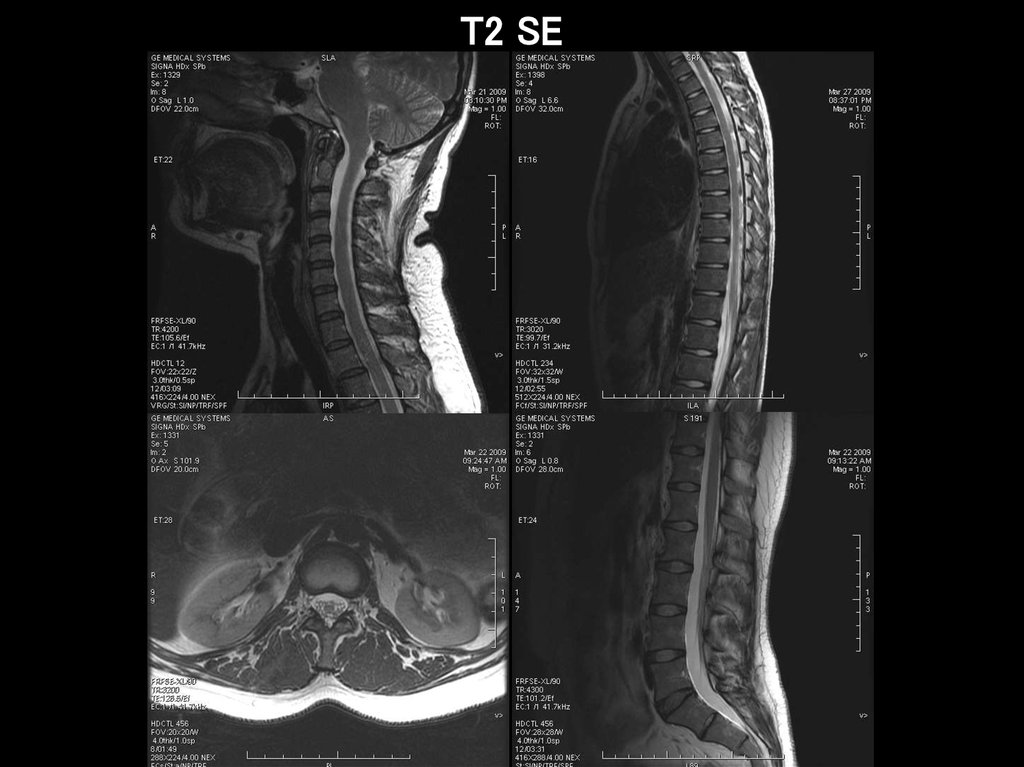

исследование позвоночника

T2 SE